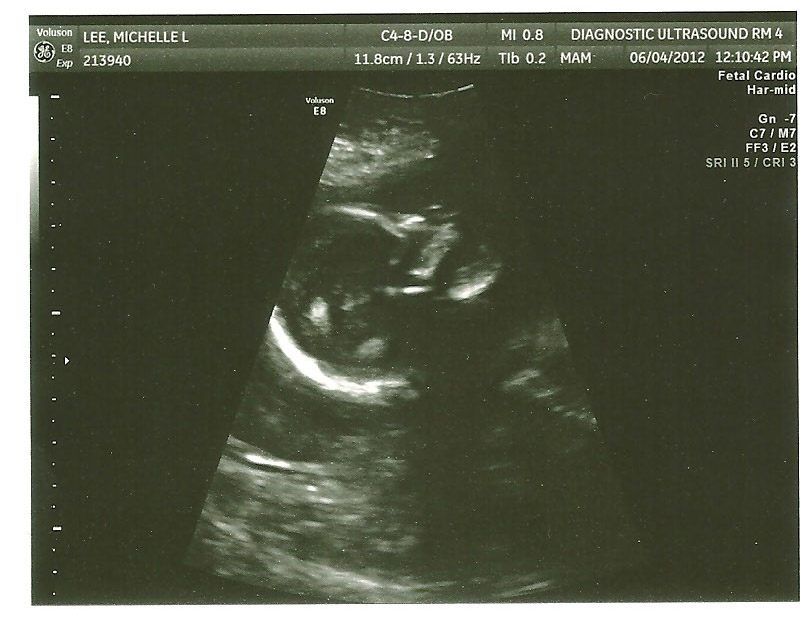

It's a GIRL!!!

Here she is with her mouth open (a preview of things to come?):

She appears to be quite healthy and growing well. The only notable finding on U/S were that I had an SCH (no surprises there) that appears to be about the same size as before as well as a low-lying placenta. I was really hoping the SCH would be significantly diminished (or gone) but that isn't the case. We're not out of danger yet, but there is much to celebrate none-the-less.